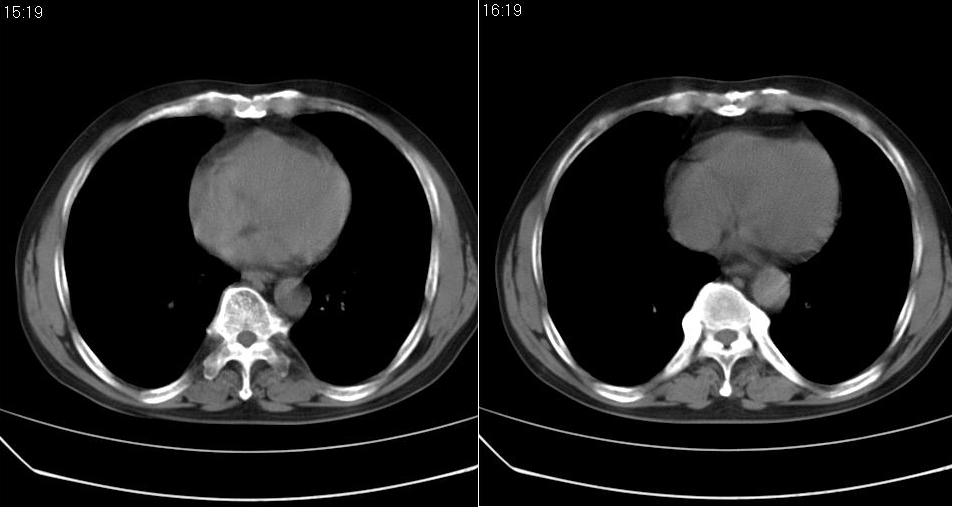

男 60岁,咳嗽,喀痰,胸闷,有吸烟史,正常图片未上传,请谅解。

左肺肿块有分叶、有毛刺,符合周围型肺癌。

考虑左肺下叶周围型肺癌可能性大。

分叶状肿块,有毛刺,有晕,有粗纹理直通肺门,支持考虑周围型肺癌

考虑肺癌建议强化